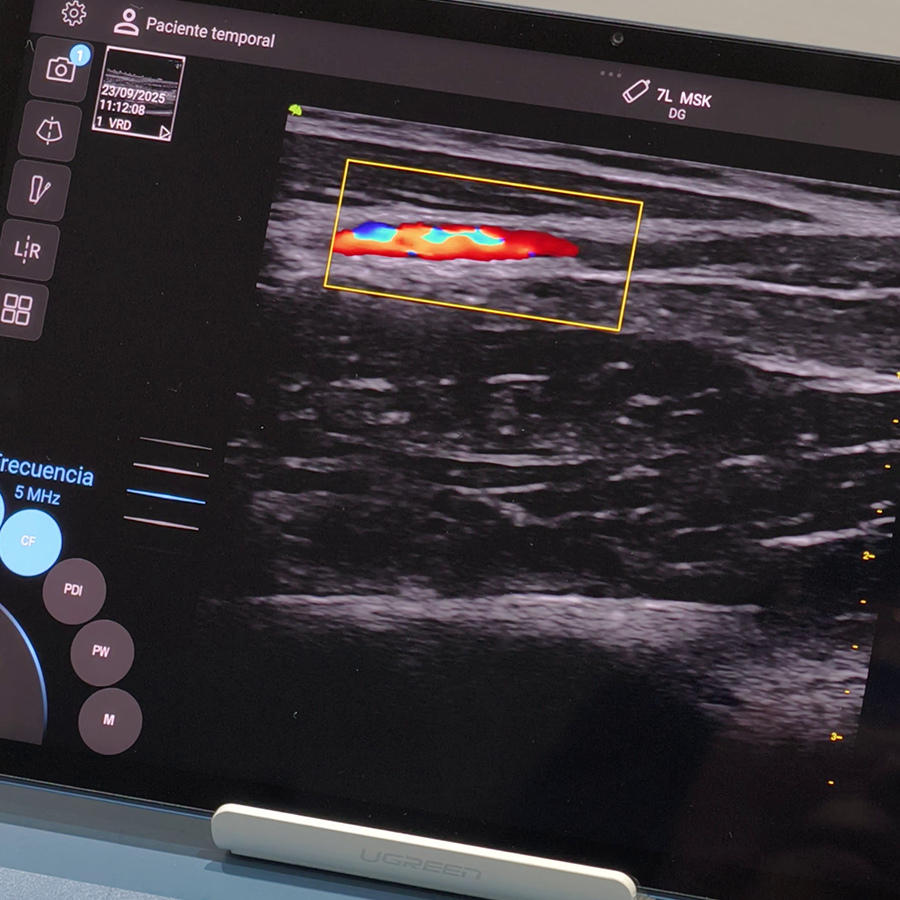

Doppler

- Modo CFM (Color)

- Modo PW (Pulsado)